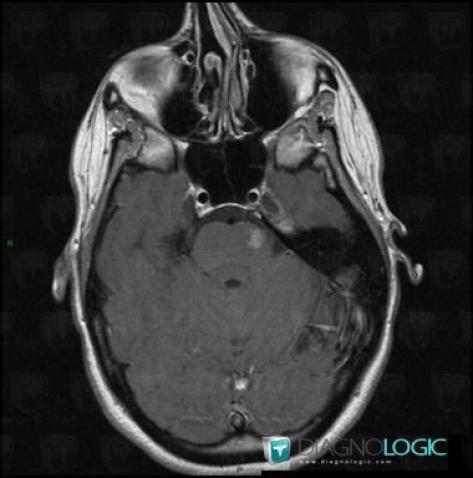

Télangiectasie capillaire, Tronc cérébral, Fosse postérieure, IRM

Voici les informations spécifiques à l'image clé ci dessus:

- Diagnostic Télangiectasie capillaire, Localisation(s) Tronc cérébral, comportant les gammes Lésion du tronc cérébralFosse postérieure, comportant les gammes Lésion infratentorielle à réhaussement modéré